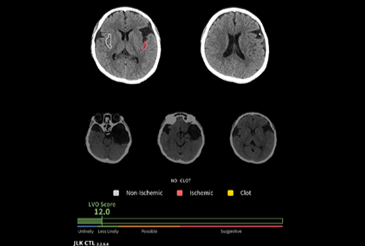

JLK-CTL은 조영제 없이 촬영한 비조영 CT(NCCT) 영상으로 대혈관 폐색 여부를 신속하고 정확하게 예측하는 AI 솔루션이다. 응급 현장에서 주로 쓰이는 비조영 CT를 기반으로 조기에 대혈관 폐색 의심 환자를 선별해 골든 타임을 확보한다. 이어지는 CTA, DWI 등 정밀 검사 대상을 신속하게 선별할 수 있어 환자의 예후 개선에 도움이 되고 불필요한 검사를 줄여 치료비 부담 완화, 국가 보험재정 절감, 필수 의료 체계 강화 등 긍정적 효과도 기대할 수 있다.

류위선 최고의학책임자는 "JLK-CTL은 대혈관 폐색 가능성을 정량적으로 제시해 의료진이 환자 치료 경로를 빠르게 결정할 수 있도록 지원한다"면서 "뇌졸중 AI 솔루션 3종 패키지가 다양한 모달리티(영상 방식)를 지원해 병원 규모나 지역 차이 없이 균일한 분석 결과를 제공하는 등 국가적인 필수 의료 서비스 강화에도 도움을 줄 수 있을 것"이라 기대했다.